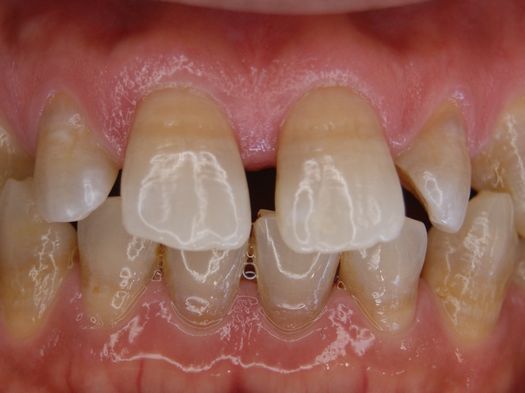

症例3

フィステル(瘻孔)があって、変色している症例。根管治療をすると、フィステルは消失。

DSC00513.JPG

DSC00520.JPG

レントゲン写真がこちら。根管治療&根管充填(この場合キャナルス&ガッターパーチャ)後。